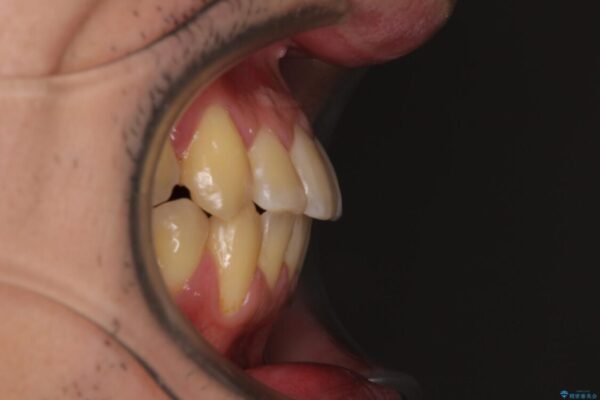

八重歯と前歯のクロスバイトを改善したいとのことで来院された患者様です。

デコボコの程度は強かったのですが、口元の突出感はなかったため、非抜歯矯正としました。

治療前

• 八重歯とクロスバイト 目立たないワイヤー装置で矯正治療 治療前画像